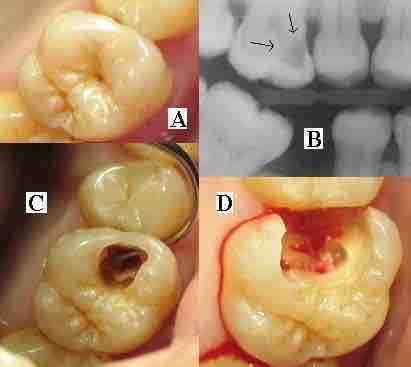

Dental Caries

(A) A small spot of decay visible on the surface of a tooth. (B) The radiograph reveals an extensive region of demineralization within the dentin (arrows). (C) A hole is discovered on the side of the tooth at the beginning of decay removal. (D) All decay removed.